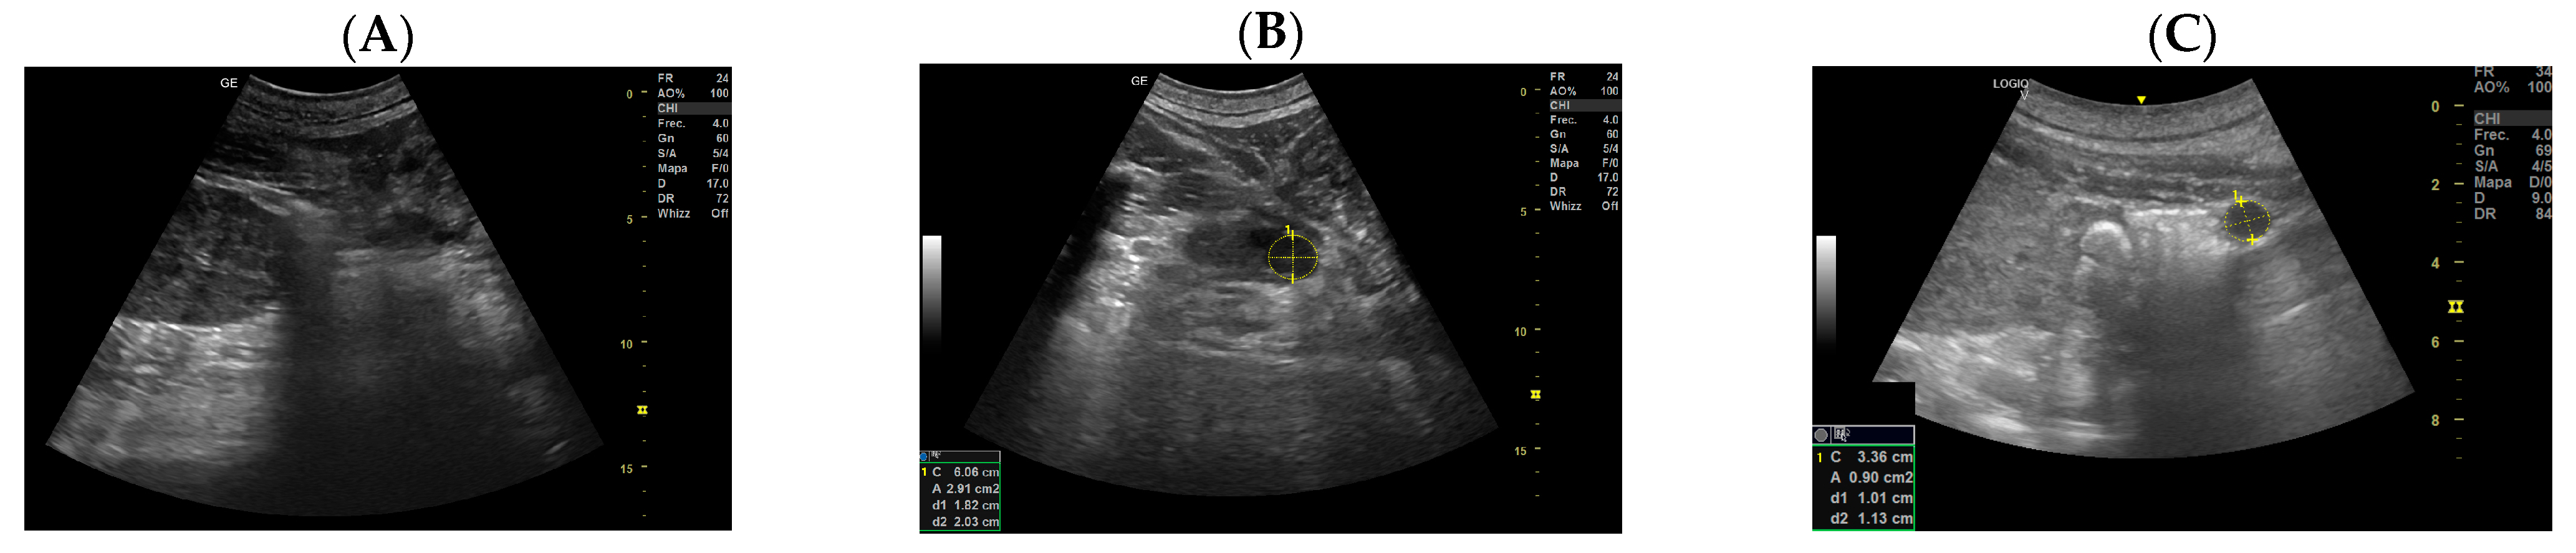

3.3. Construction of the Growth Curve of the Embryonic and Fetal Blubber Thickness

3.4. Construction of the Growth Curve of the Embryonic and Fetal Head Diameter

3.5. Construction of the Growth Curve of the Blubber Thickness